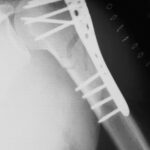

Arm Fractures are a common injury that occurs with falls, especially in aging individuals or those whose bones may not be as strong. Some of the most common fractures include the hand (scaphoid), wrist (radius), and upper arm (proximal humerus). The important thing is these fractures are not something that has to keep you from doing the activities you love.